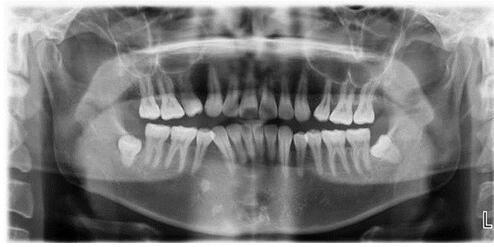

智齿要不要拔、如何避免“老掉牙”?这些常识要知道长了智齿到底要不要拔? 智齿是从门牙往里数的第八颗牙,学名叫第三磨牙,通常在18岁后开始萌出。由于个体差异,有些人上下左右四颗智齿齐全,但也有人只长一两颗,甚至不长智齿。 智齿位于牙槽骨的深处,且萌出的时间比较晚,很多情况下会因为没有足够的生长空间,导致萌出的位置、...

智齿要不要拔?如何避免“老掉牙”?这些常识要知道长了智齿到底要不要拔? 智齿是从门牙往里数的第八颗牙,学名叫第三磨牙,通常在18岁后开始萌出。由于个体差异,有些人上下左右四颗智齿齐全,但也有人只长一两颗,甚至不长智齿。 智齿位于牙槽骨的深处,且萌出的时间比较晚,很多情况下会因为没有足够的生长空间,导致萌出的位置、...

智齿发炎怎么办?除了拔除,做好这几点或也可缓解炎症!智齿也被称为智慧齿,指的是口腔内牙槽骨上最靠后的第3颗磨牙。智齿的萌出时间一般来说都比较晚,大约16~25岁之间会出现智齿。 但由于智齿长在牙槽骨的最末端,所以在长出智齿时,由于没有足够的生长空间,就会导致智齿的方向、位置以及高度受到严重影响,导致智齿发生炎症的概...